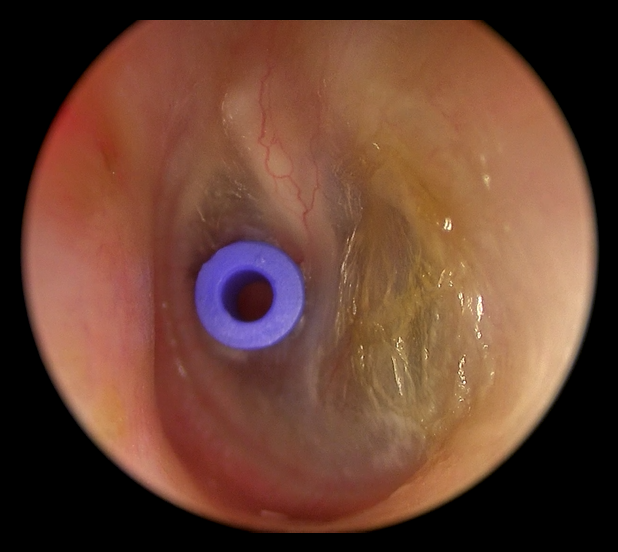

2. Cirúrgico: Colocação de Tubo de Ventilação

Em casos refratários ao tratamento clínico ou quando opta-se por uma resolução mais imediata do quandro de otite com efusão, indica-se a colocação de tubo de ventilação por meio de uma microcirurgia. É o tratamento mais eficaz nos casos crônicos. Por meio de uma pequena incisão do tímpano, denominada timpanotomia, cria-se uma via secundária de ventilação do ouvido médio, garantindo aeração contínua e absorção do líquido. Em seguida, posicina-se o tubo de ventilação no local nessa incisão para garantir um ventilação contínua do ouvido médio. O tubo de ventilação é expulso espontaneamente pelo tímpano, sem necessidade de nova cirurgia para sua retirada.

Um estudo publicado no New England Journal of Medicine (2020) com mais de 600 crianças mostrou que a colocação de tubos reduziu significativamente o tempo de otite média com efusão, melhorou a audição e diminuiu o uso de antibióticos, com taxa de sucesso acima de 85%.